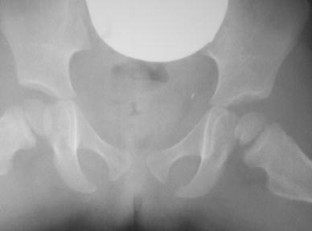

Inflammatory or septic arthritis due to Mp is an extremely unusual manifestation in children, and the functional outcome of the joints is difficult to be predicted. Two cases with Mp infection are presented. The first patient had positive PCR for Mp after hip aspiration and arthrotomy with thorough irrigation and debridement. A flattened femoral head was detected during the follow-up, which became quite spherical a year after. An arthrotomy with medial synovectomy of the knee was performed in the second patient. Lack of full knee extension was presented during the first 3 months, which gradually decreased to 7° in the final follow-up. The suspicion of Mp infection with extra-pulmonary involvement in children is mainly based on clinical, epidemiological and radiological data, but laboratory testing is required for confirmation. Rapid diagnosis of probability consists of serum tests, and their results are essential for early therapeutic planning. The direct diagnosis of Mp DNA through polymerase chain reaction (PCR) provides specificity and sensitivity. Very few cases of arthritis associated with Mp infection have been published but not with the severity of our cases. Clinical suspicion of Mp infection is of great importance, and the outcome depends on early diagnosis and specific treatment.

Fig. 3